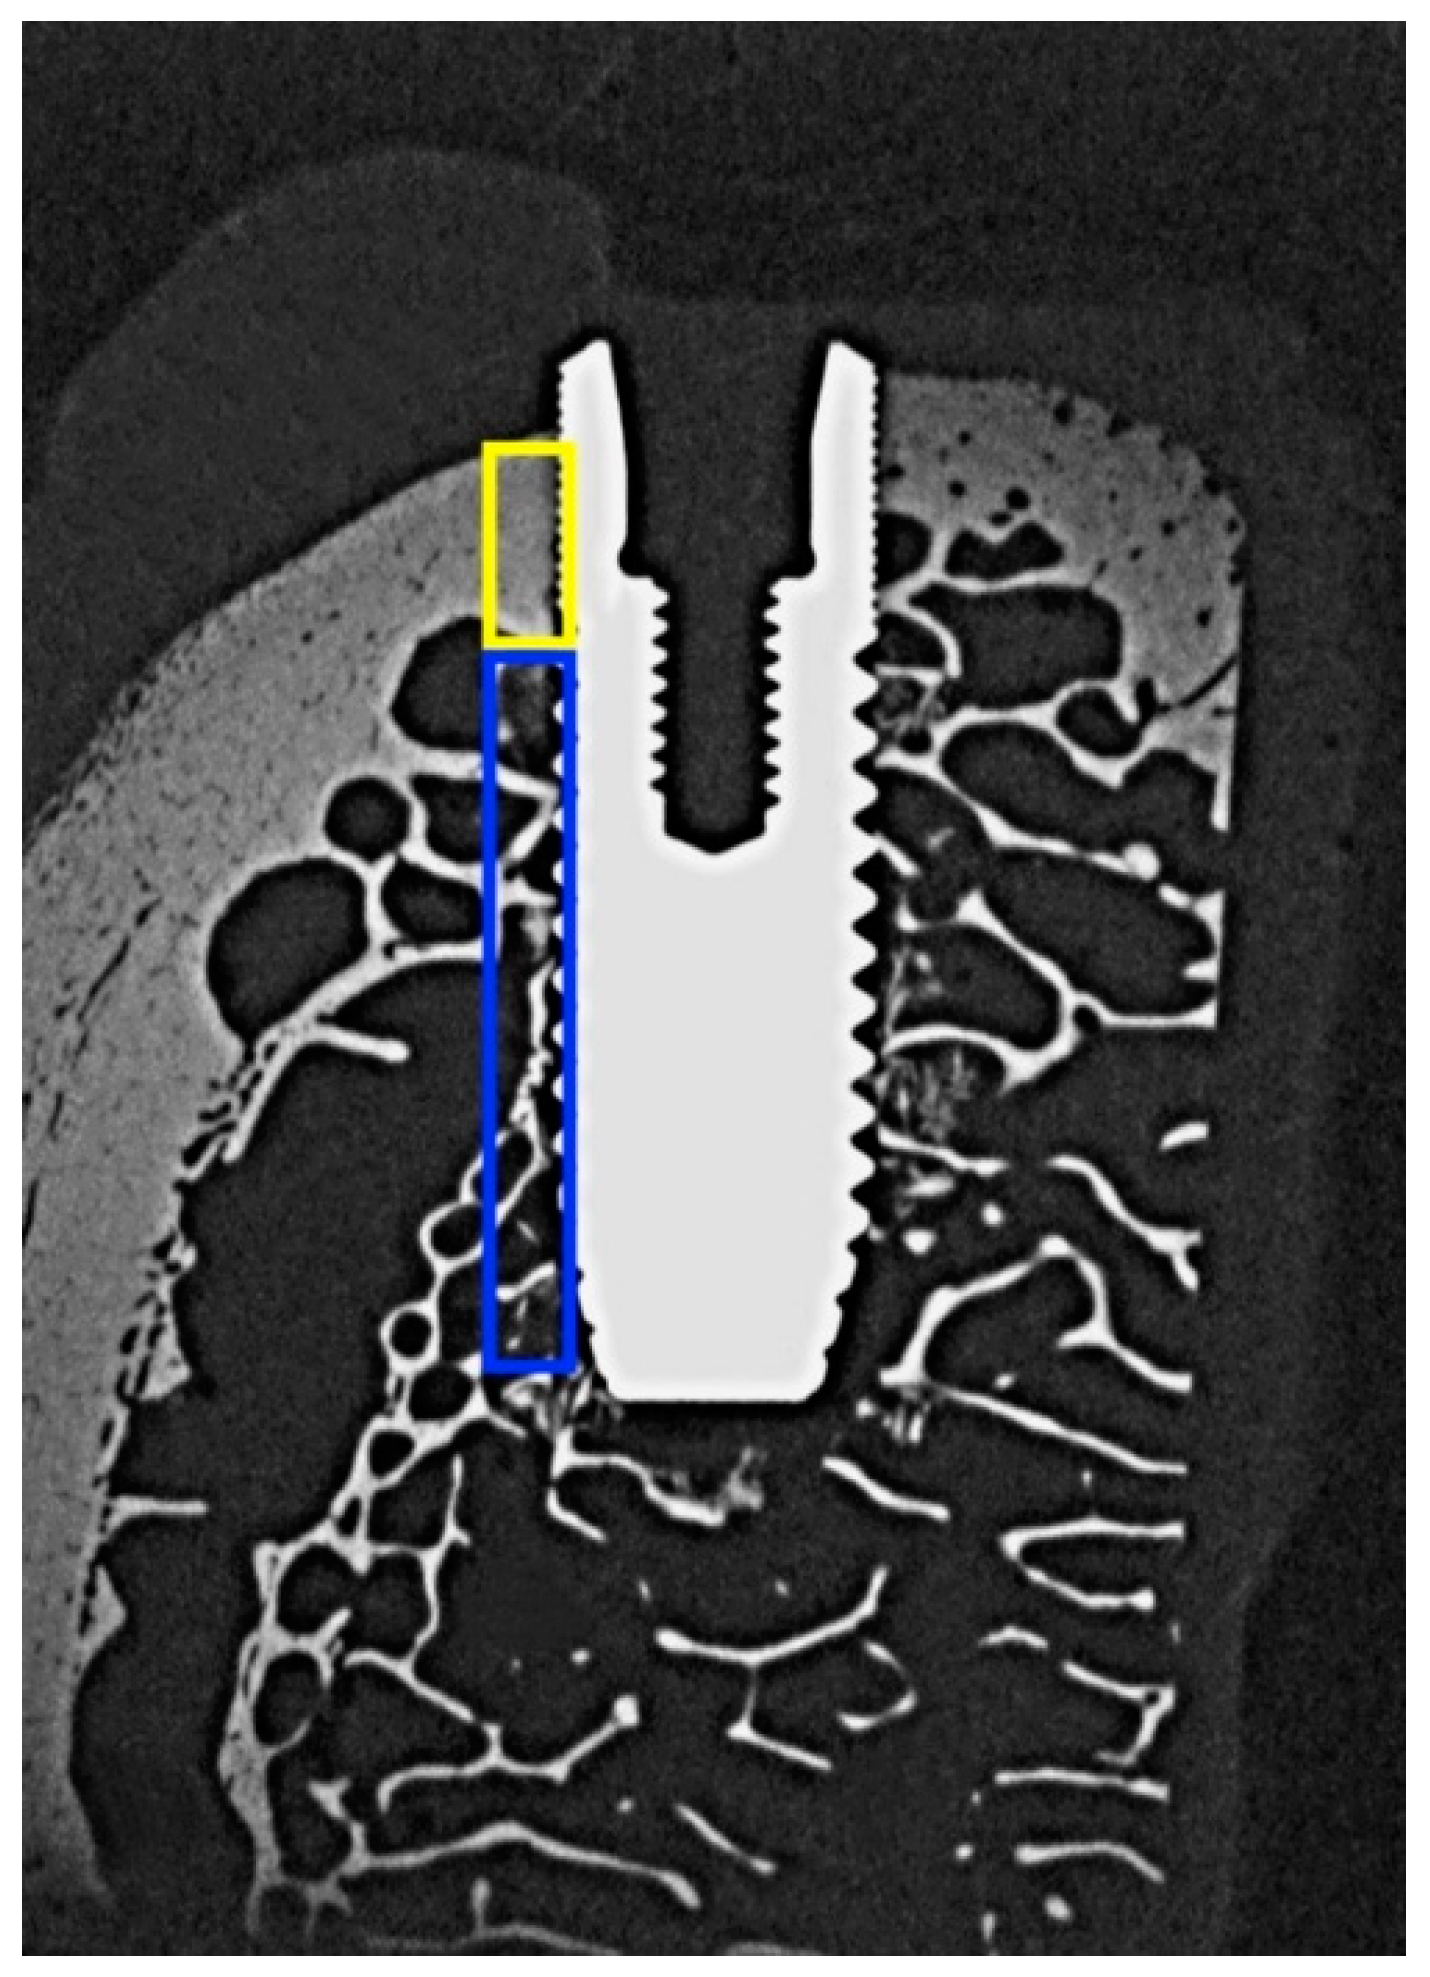

2. Materials and Methods

2.2. Histologic Analysis